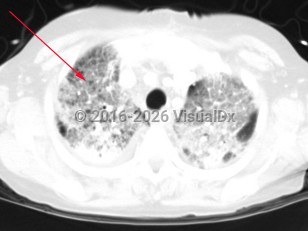

Haemophilus influenzae pneumonia

Haemophilus influenzae is a small, gram-negative, facultative anaerobic organism with a variable appearance on clinical specimens ranging from coccobacilli to long filaments. In addition to causing serious invasive infection, this organism is also an important etiology of both community-acquired and hospital-acquired pneumonia.

Symptoms include fever, cough, and shortness of breath. Symptoms may differ depending on the type of pneumonia (either segmental or bronchopneumonia). Patients with a segmental pneumonia can present with abrupt onset of fever, pleuritic chest pain, and sore throat. These patients tend to develop bacteremia more frequently than those with bronchopneumonia. Patients with bronchopneumonia can present with constitutional symptoms, tachypnea, and a mild fever. Haemophilus influenzae more commonly presents as a bronchopneumonia.